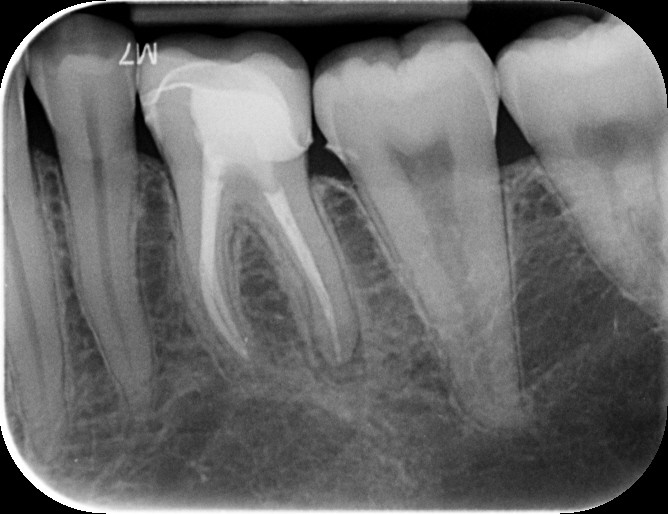

Pre-operative Assessment

Pre op PA showing periapical radiolucency around 36D root apex.